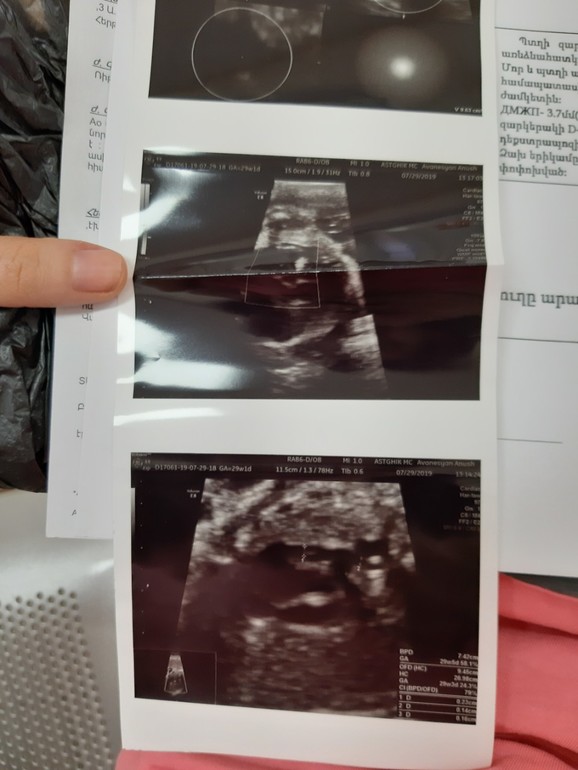

Здравствуйте, доктор, у меня беременность 30 недель. Все скриннинги и анализы всегда в норме бывали, на 24 неделе поставили впс у плода, но почки всегда в норме были, а теперь по доплеру обнаружили что левая почка кистозно изменена. Сказали вторая почка нормальная, скажите, пожалуйста, может ли при рождении проблема сама решиться, и как эти аномалии раньше не выя

влялись, могу приложить снимки доплер, спасибо